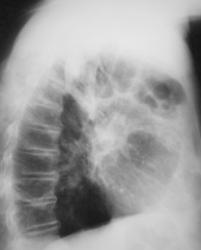

Иллюстрации 2 и 3. Томограммы.

Иллюстрация 4. Томограмма – срез 5 см. Высказано предположении о наличии хронической пневмонии в задне-базальных сегментах.

Иллюстрации 5. На срезе 10 см. справа в корне создается впечатление «наличия увеличенных бронхопульмональных лимфатических узлов» и некоторое «сужение промежуточного бронха».